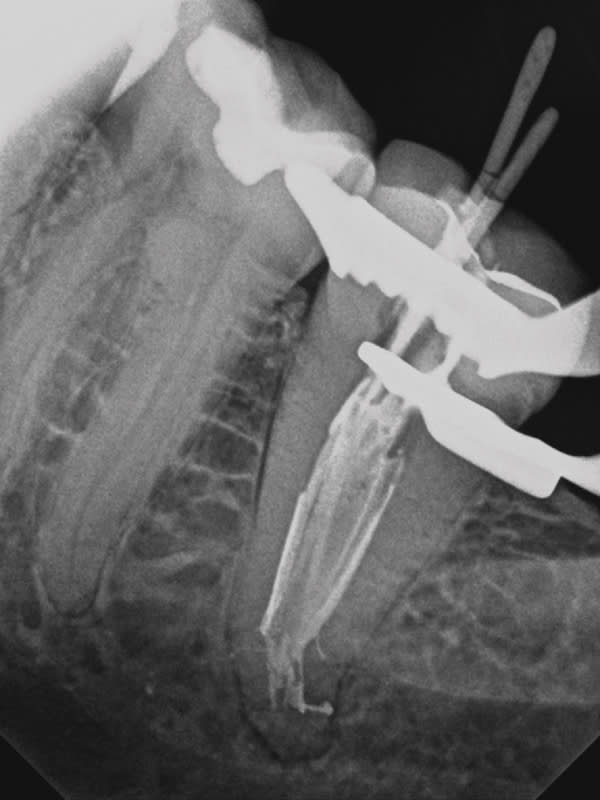

A C-shaped molar root canal can cause even seasoned clinicians to question whether to perform treatment in a one- or two-visit procedure. Tortuous anatomy and unusual root complexities make it difficult to clear all the tissue from the root canal system. Clinicians often opt for sonic or ultrasonic irrigation and a two-visit procedure to assure a positive clinical outcome. In this case, GentleWave® Procedure Multisonic Ultracleaning® technology (Sonendo, sonendo.com) was used to treat irreversible pulpitis in a C-shaped lower second molar, which is often difficult to address. After administration of anesthesia, and with the use of a dental microscope (Leica M320, Leica Microsystems, leica-microsystems.com), conservative straight line access was achieved, and three canals were located, measured, and instrumented. The GentleWave Platform was then built onto the tooth, the Procedure Instrument attached to the GentleWave Console, and the GentleWave Technology finished the procedure. Eight minutes later, the platform was removed, the canals dried, and the canal system filled. Upon completion of the GentleWave Procedure and warm vertical obturation the results were astonishing as evidenced in the final radiograph.

Endodontic challenges such as a C-shaped molar root canal can be treated successfully in one visit with minimal instrumentation and the GentleWave Procedure.

Closed-loop Multisonic Ultra-cleaning technology reaches deep into lateral canals and microscopic tubules to remove tissue, debris, biofilm, and bacteria. It also helps preserve the integrity of the tooth by leaving dentin intact.

With advanced fluid management, the self-contained GentleWave System delivers the precise concentration of procedure fluids, resulting in the simultaneous ultracleaning of each canal from crown to apex.